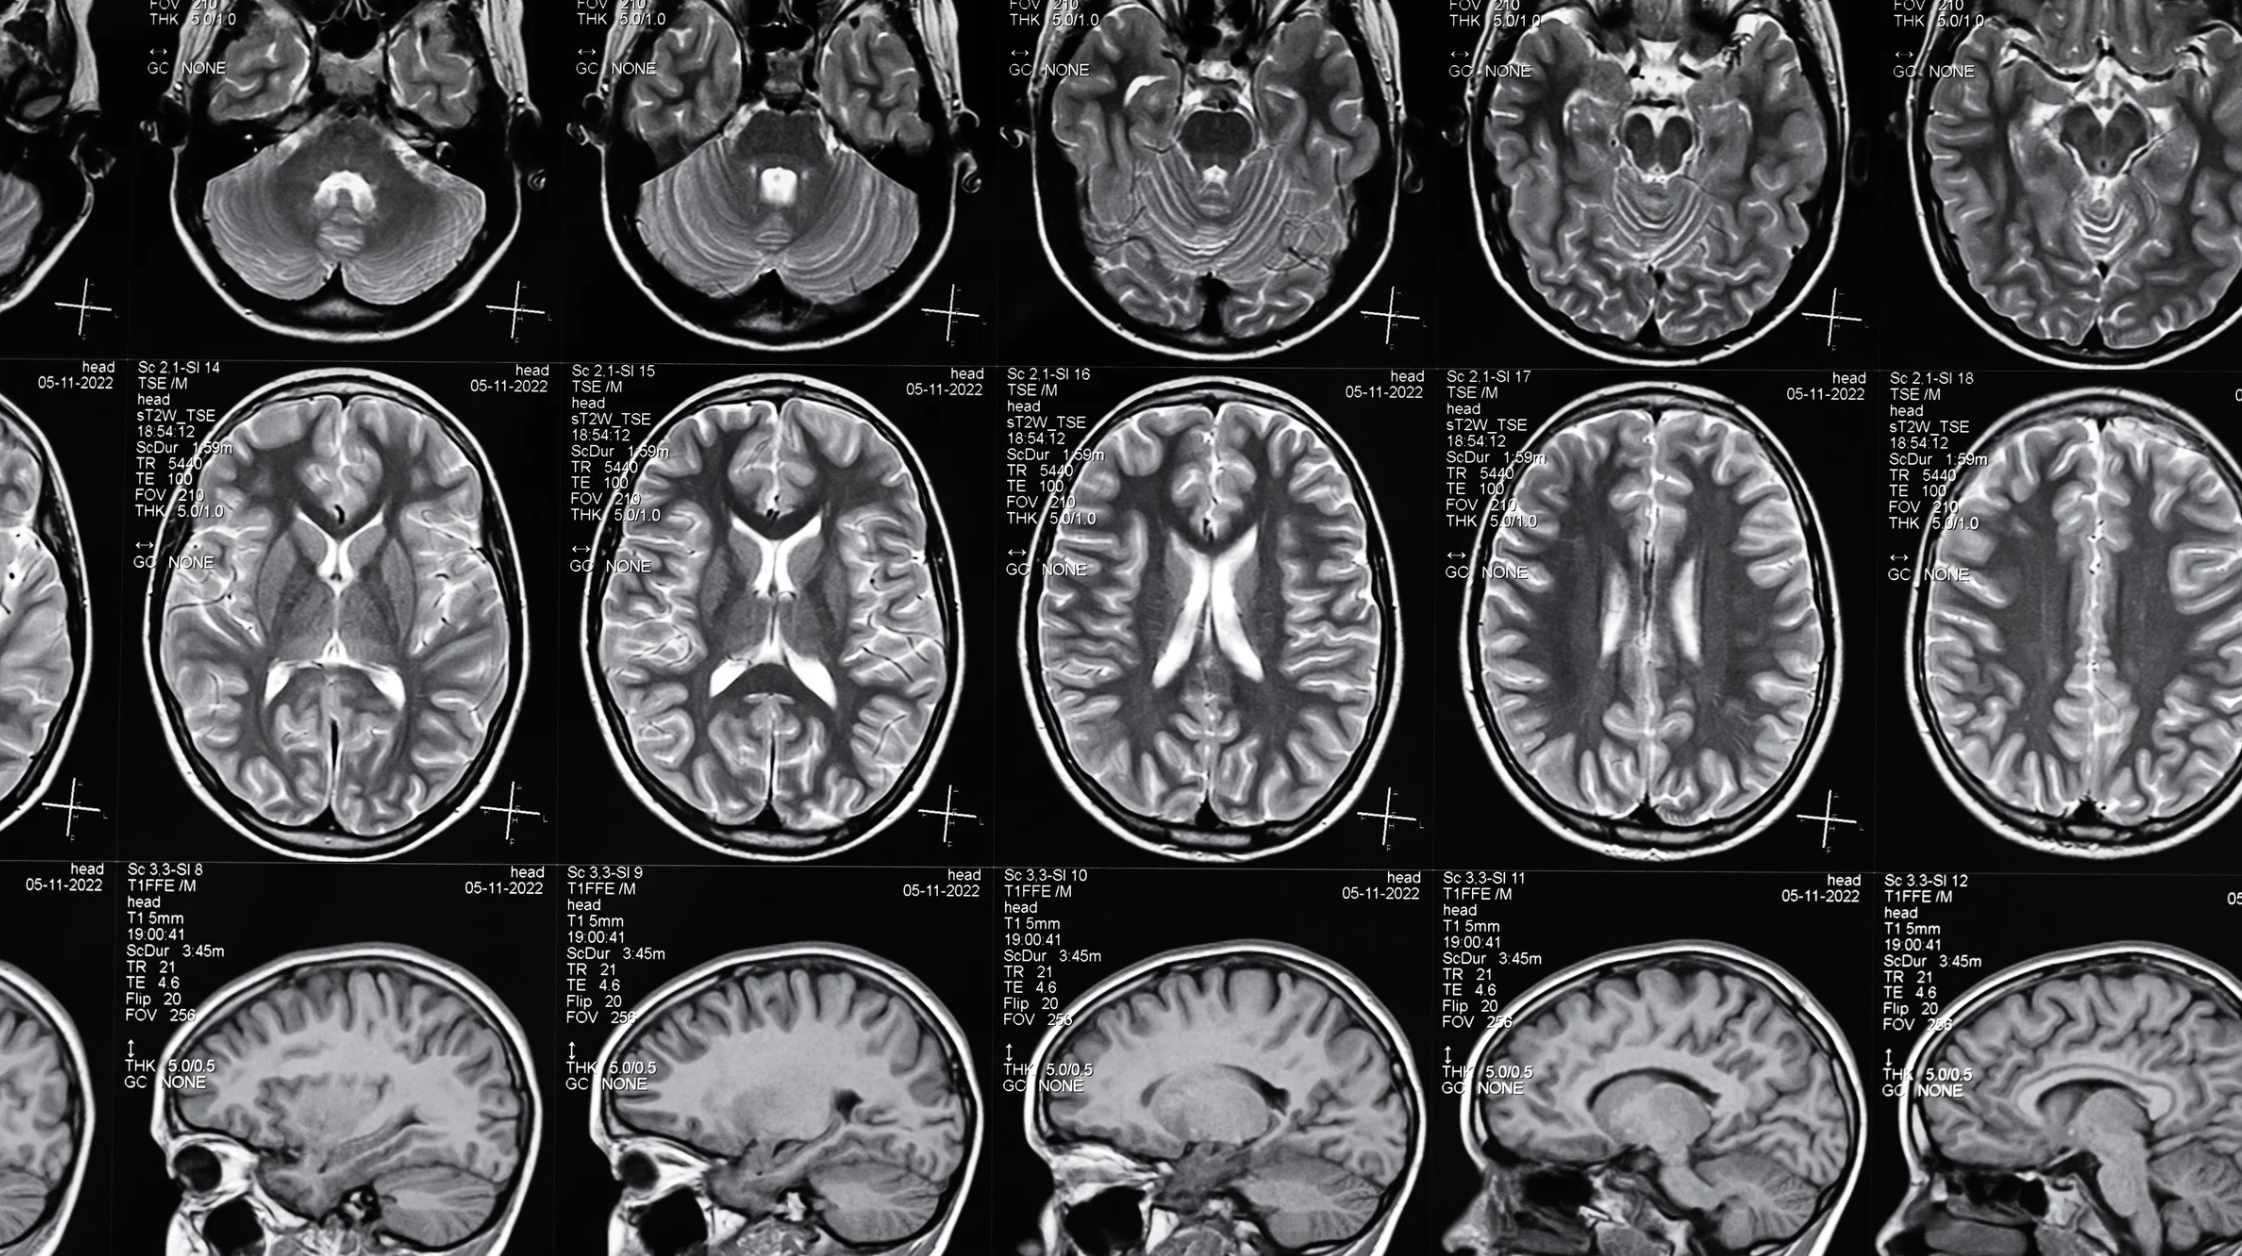

What Are The Different Types Of Traumatic Brain Injuries?

There are three main types of traumatic brain injuries:

- Mild Traumatic Brain Injury or concussion

- Moderate Traumatic Brain Injury

- Severe Traumatic Brain Injury

A moderate or severe closed head injury can be caused by a bump, blow, or jolt to the head or by a penetrating injury to the head. A doctor’s failure to diagnose, or delay in response, to a traumatic brain injury case can have lasting impacts.